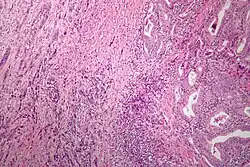

Microscopic image of anaplastic thyroid carcinoma. H&E stain.

Anaplastic tumors have a high mitotic rate and frequently invades the local blood and lymphatic vessels.[5] Cellular death is frequently visualized on microscopic images.[2] The presence of regionally swollen lymph nodes in older patients in whom needle aspiration biopsy reveals characteristic vesicular appearance of the nuclei supports a diagnosis of anaplastic carcinoma. Microscopic images of ATC usually show inflammatory cells from the immune system such as T cells and macrophages.[2]

ATC is divided into several different subclasses based on its microscopic characteristics. These include sarcomatoid, squamoid, osteoclastic, paucicellular, rhabdoid, and carcinomasarcoid variants.[2] As of 2019, despite the fact that these ATC subtypes are recognized, this classification has not led to differences in management.[2] ATC is always considered to be stage IV when it is diagnosed.[6]